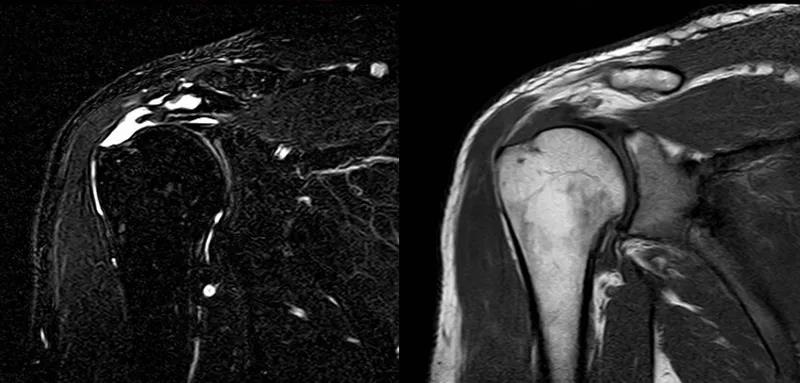

图21 斜冠状位(临床常用)a.T2,b.T1

图24 a.肩袖全层撕裂;b.正常MRI